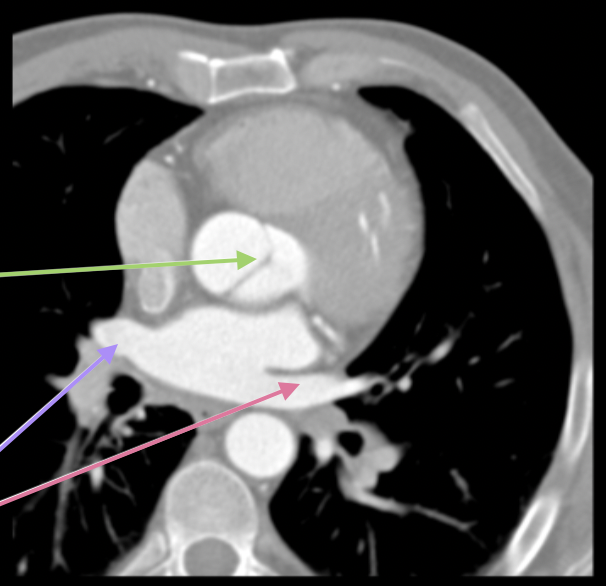

New cards

valva aortae

grön